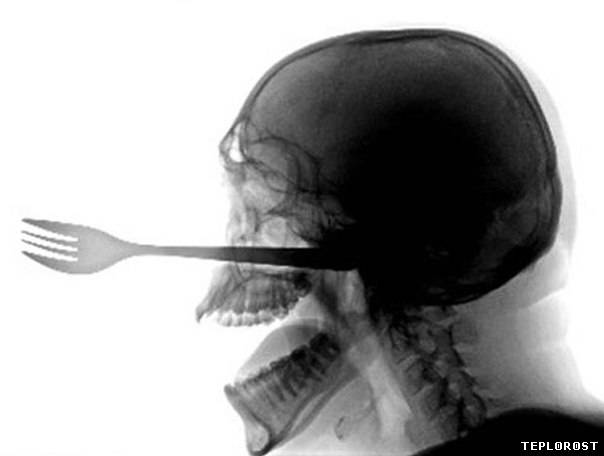

Этот пациент проглотил столовые пиборы

Вилка в черепе человека